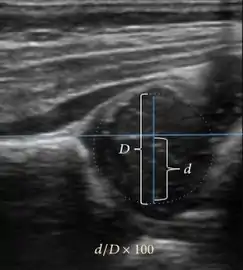

Ultrasound

Ultrasound is the first-choice technique for diagnosis of newborns hip dysplasia. In experienced hands with appropriate technology, ultrasound can also be useful during the first year of life. Some European healthcare systems encourage universal ultrasound screening in neonates between the sixth and eighth weeks. Although it shows higher initial costs caused, it leads to significant reduction in the total number and overall costs of dysplastic hips undergoing operative and nonoperative treatment.[1]

Ultrasound allows categorizing pediatric hips, according to Graf’s criteria, in four main types: normal, immature, and dysplastic (subluxed and dislocated). This classification is based on measurements of the acetabular inclination angle (alpha), cartilage roof angle (beta), and infant age. The femoral head coverage can also be determined by dividing the length of the femoral head covered by the acetabular fossa and the diameter of the femoral head. Its lower normal limits are 47% for boys and 44% for girls (Figure 11).[1]

Figure 11:

Useful ultrasound measures in neonatal hip sonography, alpha and beta angles.[1]

Measurement of femoral head coverage.[1]